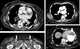

Cardiomegaly

Cardiomegaly (sometimes megacardia or megalocardia) is a medical condition in which the heart is enlarged. As such, it is more commonly referred to simply as "having an enlarged heart". [Source: Wikipedia ]